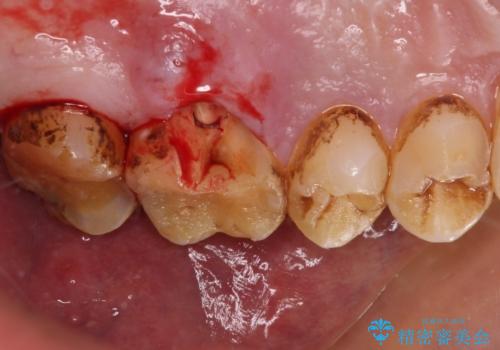

- 食事で堅いものを噛んだ時に歯が欠けてしまったとのことで来院された患者様です。

咬合面に大きな修復物が入っており、その境目から破折し、歯肉の内側の歯根にまで破折が及んでいました。

残念ながら神経組織が露出しており、根管治療が必要となっていたため、まずは根管治療を行うこととしました。

根管治療後に、歯根にまで及んでしまった破折部分を適切な位置に変更するため、歯槽骨の削除を伴う外科処置を行い、その後補綴治療を行うこととしました。